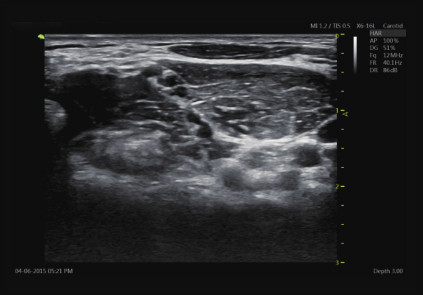

臂丛神经